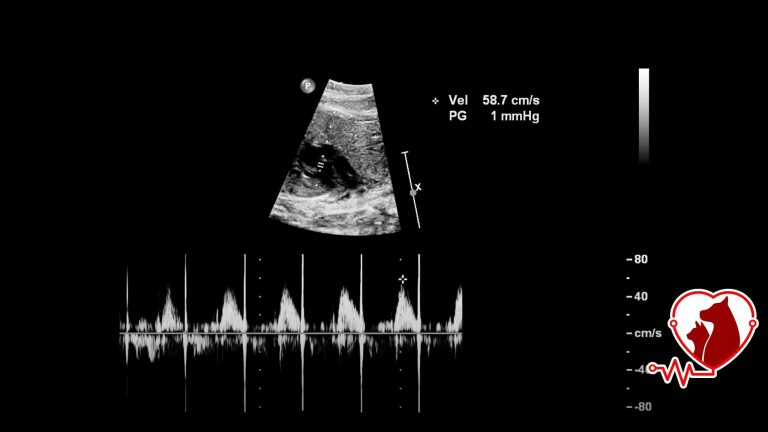

Ultrason

Petheart'ta kedi, köpek, tavşan, için özel programlanmış ultrason ile gebelik, organ ve sistem muayeneleri yapılır.